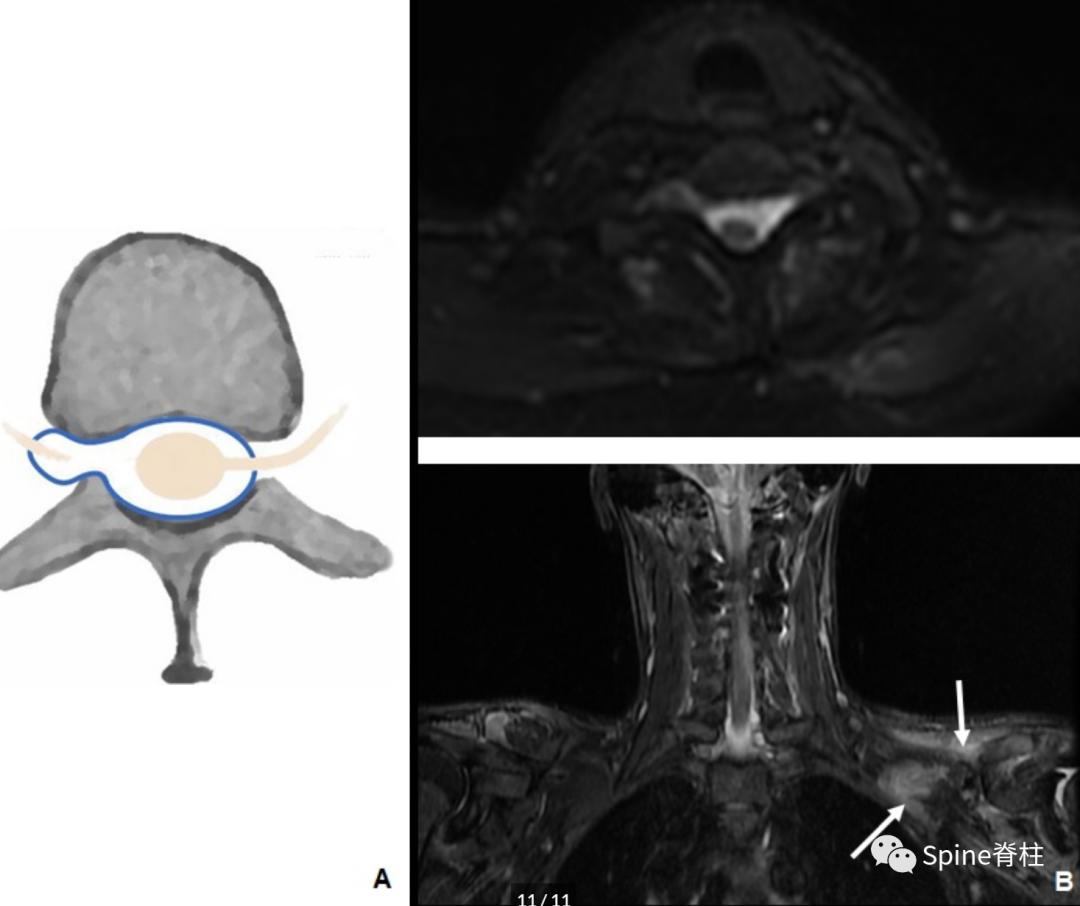

单个的神经根袖扩张多见于创伤后或手术后假性脊膜膨出,常见于臂丛神经损伤。在这种情况下,神经根袖的破裂使得脑脊液从蛛网膜下腔漏出(下图)。类似于神经根袖憩室,多数患者是无症状的。

30岁左臂丛神经病变后进行性左侧脊髓病患者。模式图提示右侧假性脊膜膨出的典型外观(A)。横断面STIR提示左侧膨大的神经根袖囊肿压迫脊髓(B)。冠状STIR(B)显示左冈上下肌失神经支配性水肿(箭头)